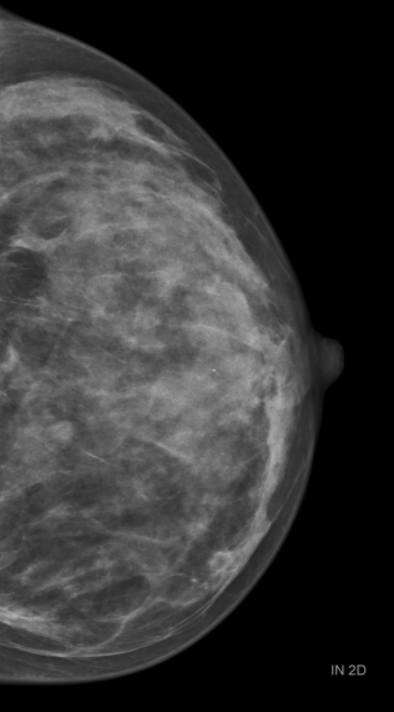

Затем были проведены рентгеновская маммография и МРТ молочной железы.

В результате исследований у пациентки был диагностирован пролиферативный DCIS правой молочной железы (протоковая карцинома молочной железы in situ).

Затем была проведена стериотактическая вакуумная биопсия под контролем рентгеновской маммографии ,в результате чего была диагностирована инвазивная карцинома правой молочной железы.